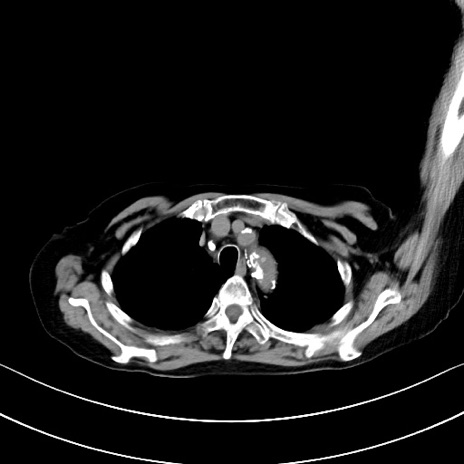

【症例】90歳代女性

【主訴】腹痛・嘔吐

【現病歴】 食欲低下、嘔吐があり昨日他院受診。肺炎と診断され入院となる。入院後より腹部全体に圧痛あり。胃管留置され経過みていたが、症状持続するため、

当院転院となる。

【既往歴】胸椎圧迫骨折、胆石症

【身体所見】腹部:中央に激痛あり、圧痛あり、反跳痛不明

【データ】WBC 17100、CRP 18.82